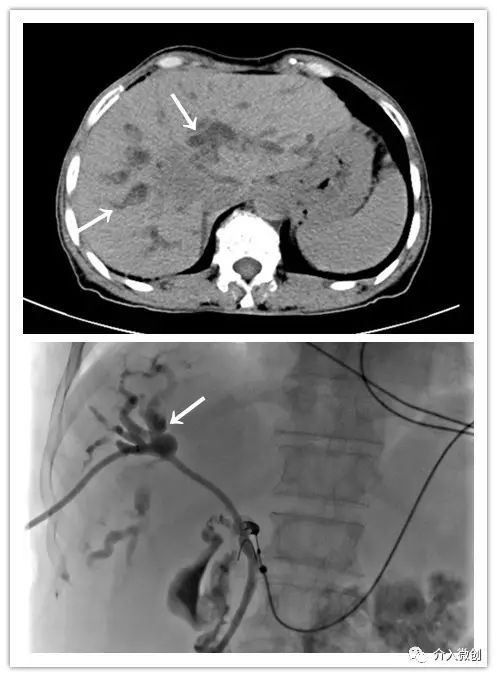

肿瘤侵犯肝门部胆管汇合区

肿瘤侵犯压迫肝门部胆管导致胆道梗阻,置入胆道引流管行胆汁引流减黄